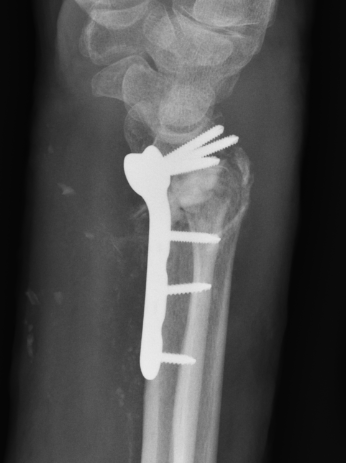

Malunion

www.boneschool.com/distal-radius-fracture-malunion